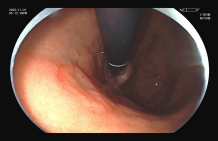

图示:食管早癌在内镜下NBI观察呈片状褐色改变,ME-NBI观察,微血管扭曲、紊乱。